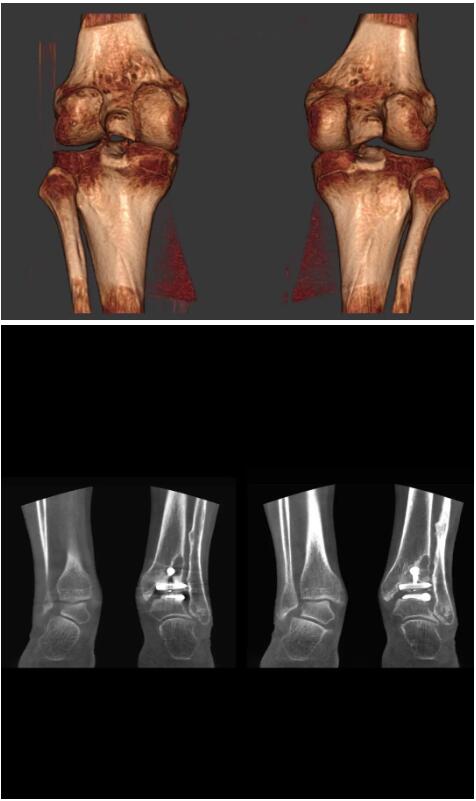

而患者站著做足部或者踝部做CT檢查還有個好處是,可以檢查患者在負(fù)重的情況下,骨關(guān)節(jié)的真實情況,而躺著做CT掃查時未必能看出來。負(fù)重CT掃查特別是對于受傷的運動員或者舞蹈員來說意義更大,能夠更準(zhǔn)確地評估傷情,幫助他們盡早復(fù)原。

以下是這些“特立獨行”的CT所拍出來的圖像: